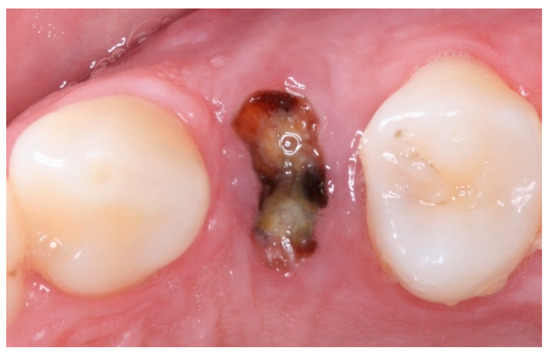

2. Materials and Methods

2.3. Pre-Surgical Procedures

2.4. Groups